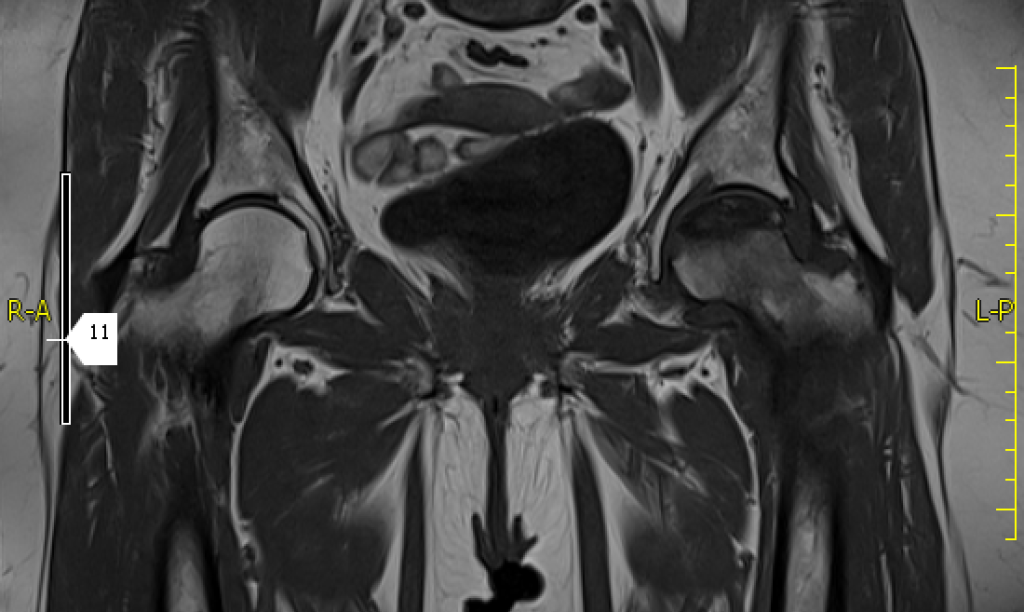

La combinación de 2 regiones hace posible el estudio conjunto de caderas y articulación sacroilíaca o valoración de columna dorsal y lumbar.

La resonancia magnética es una prueba irremplazable en la valoración de ciertas áreas anatómicas como el musculoesquelético (rodillas, hombro, caderas…) y neurológicos (columna, cerebral,…).

Se utiliza para todas las áreas del cuerpo y es esencial en musculoesquelético y sistema nervioso.